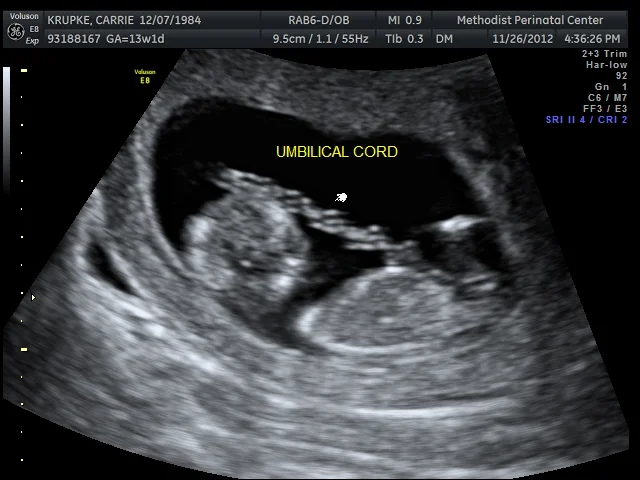

*that we were able to see and hear the heartbeat and get an audio recording. (Gerard thinks I have a train growing inside me. And judging by this photo, our child is already wielding a sword.)